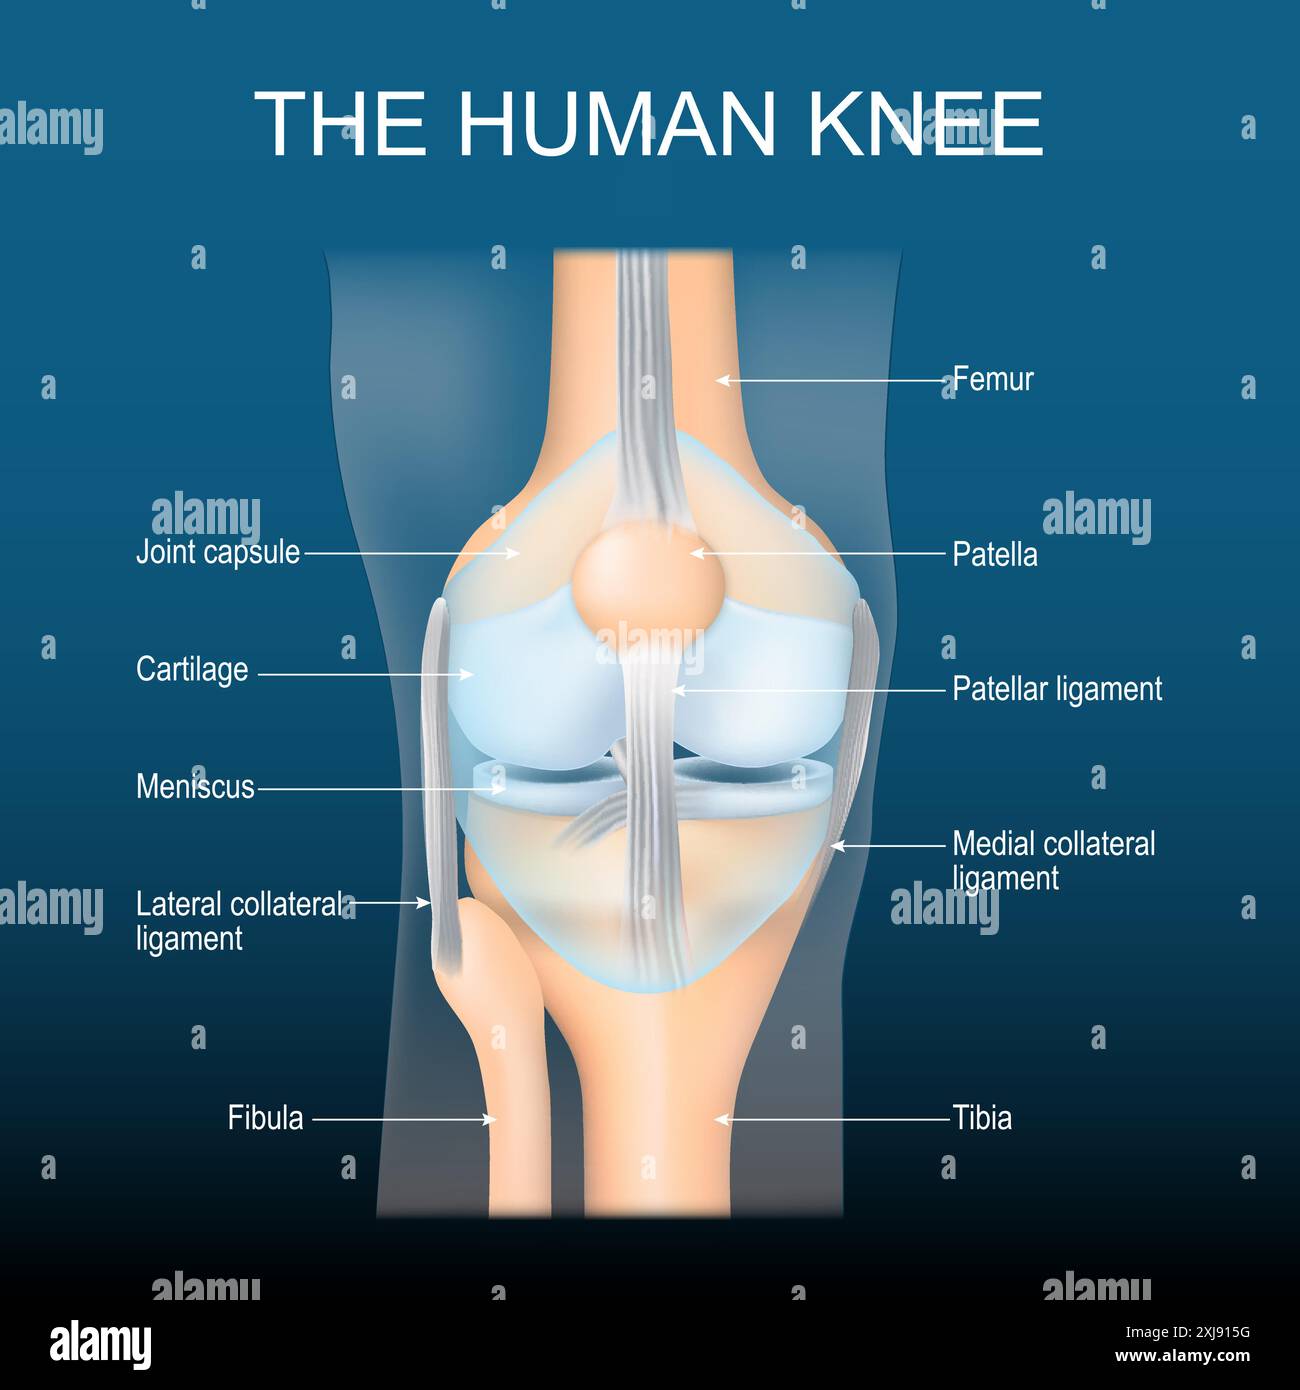

Anatomie du genou. Structure d'articulation du genou. Vue de face du genou humain avec effet lumineux. Joint bleu transparent réaliste sur fond sombre. Poster avec tex Illustration de Vecteurhttps://www.alamyimages.fr/image-license-details/?v=1https://www.alamyimages.fr/anatomie-du-genou-structure-d-articulation-du-genou-vue-de-face-du-genou-humain-avec-effet-lumineux-joint-bleu-transparent-realiste-sur-fond-sombre-poster-avec-tex-image613625196.html

Anatomie du genou. Structure d'articulation du genou. Vue de face du genou humain avec effet lumineux. Joint bleu transparent réaliste sur fond sombre. Poster avec tex Illustration de Vecteurhttps://www.alamyimages.fr/image-license-details/?v=1https://www.alamyimages.fr/anatomie-du-genou-structure-d-articulation-du-genou-vue-de-face-du-genou-humain-avec-effet-lumineux-joint-bleu-transparent-realiste-sur-fond-sombre-poster-avec-tex-image613625196.htmlRF2XJ915G–Anatomie du genou. Structure d'articulation du genou. Vue de face du genou humain avec effet lumineux. Joint bleu transparent réaliste sur fond sombre. Poster avec tex